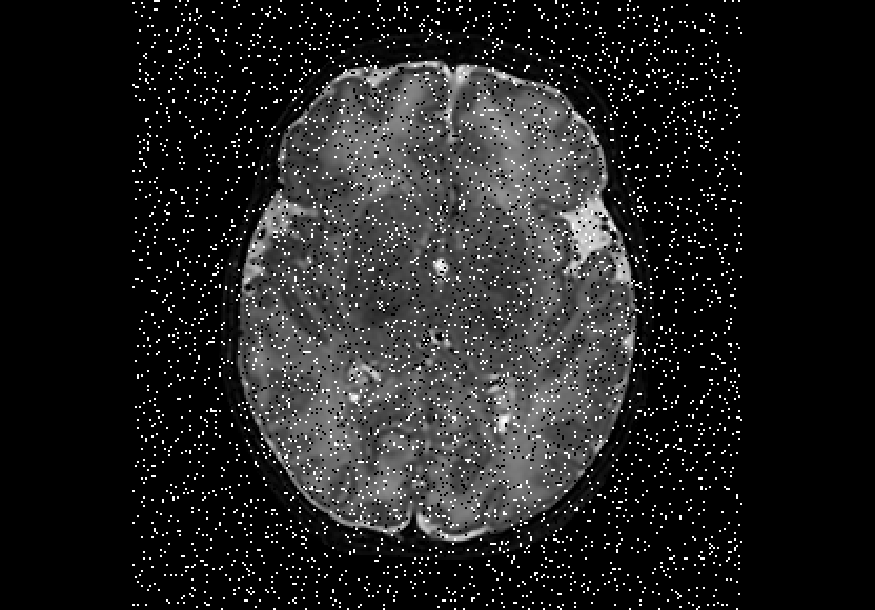

We also explored impulse noise corruptions, such as those introduced by noisy communications channels, faulty memory locations, or damage in channel decoders [6]. The impulse noise generating filter we used in this study is based on the salt-and-pepper (SNP) technique, which randomly generates black and white pixels on the image of interest. The function we used takes into account a parameter called prob, where 0 prob 0.5. A random number is generated for each pixel; if it is less than prob then the function paints the pixel with black, if it is greater than 1-prob then it paints the pixel with white, otherwise the pixel is left unchanged. In other words, the higher the value of prob, the noisier the output can become. We used different values for prob, in particular prob ={0.01, 0.03, 0.05, 0.07, 0.10, 0.15, 0.20}, to create seven different noisy datasets named snp_prob. Examples of axial slices are shown in Figure 4.